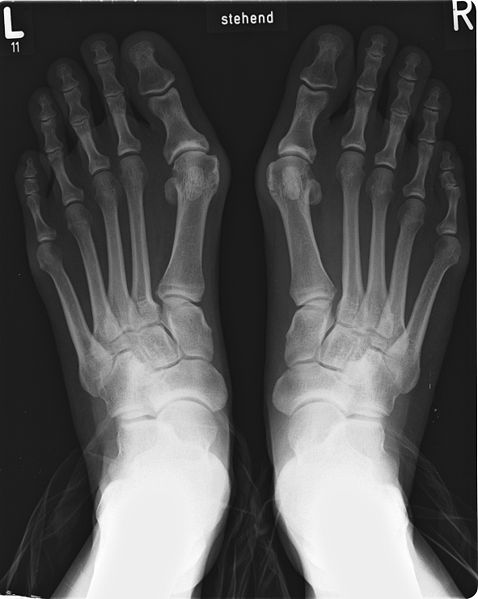

Röntgenuntersuchung des Spreizfußes

Im Röntgenbild kann der Arzt die veränderten Winkel zwischen den Mittelfußknochen messen, um so das Ausmaß des Spreizfußes abzuschätzen. Das Röntgenbild sollte unter Belastung durchgeführt werden. Der Patient muss also stehen und sein ganzes Körpergewicht auf den Fuß bringen. Anhand der Bilder erkennt der Arzt auch Folgeschäden an den Gelenken. Indirekte Zeichen für eine Instabilität, z. B. die Lisfranc-Gelenklinie (gedachte Linie zwischen Fußwurzel und Mittelfußknochen), können sichtbar gemacht werden.